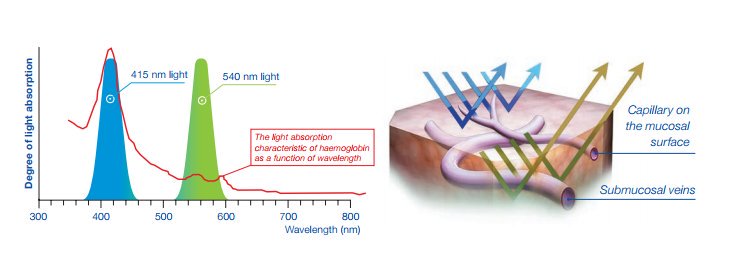

- Технология визуализации в узком спектре NBI, использующая свет определенной длины волны для получения яркого и контрастного изображения структуры слизистой и кровеносных сосудов. NBI — лидер эндоскопического рынка по ранней диагностике рака и других патологических состояний. Узкоспектральная визуализация позволяет диагностировать патоморфологические изменения в тканях даже в случаях, когда осмотр в классическом белом свете не дает результатов.